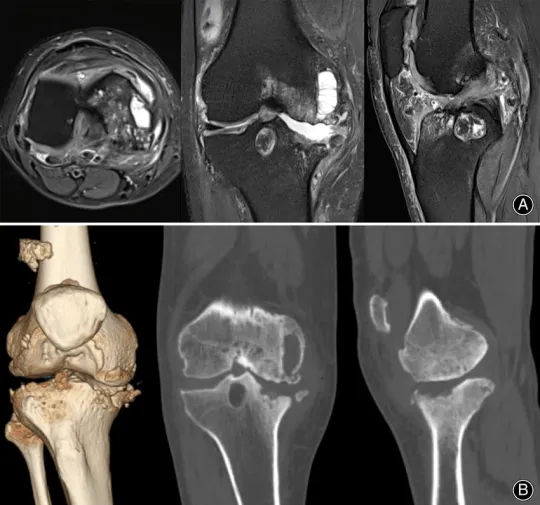

(А) - МРТ коленного сустава, (Б) - КТ коленного сустава